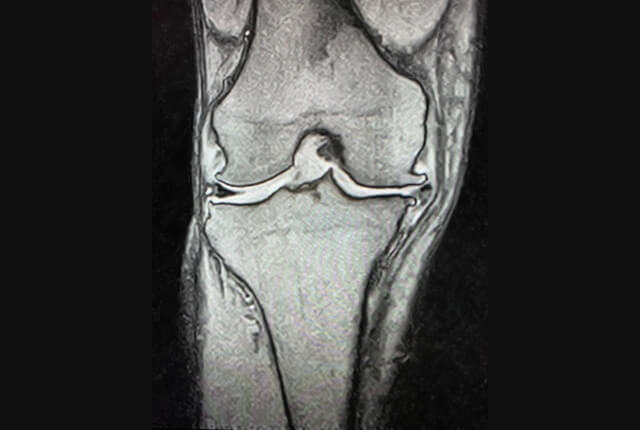

半月板の断裂形態

• 縦断裂

• 横断裂

• 水平断裂

• フラップ状断裂

• バケツ柄状断裂

• 変性断裂